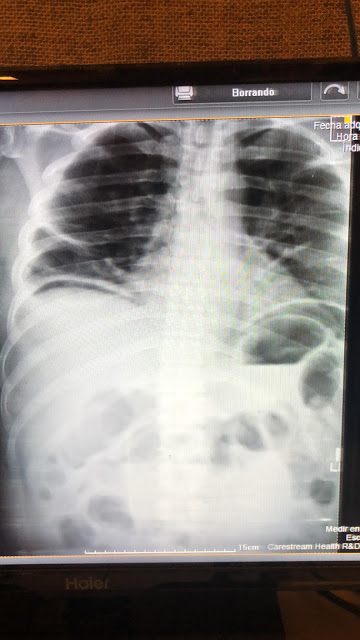

The above x-ray was done on the same 6 year old girl, finding significant constipation. We did the x-ray to see if there was concomitant constipation to see if ‘dysfunctional elimination syndrome’ was the cause of her symptoms or certainly an odd neurological disorder (she did not have any other neuro findings on exam). We are still working on caring for this little girl and appreciate prayers for her. We are thankful that her mother finally is pursuing treatment for her condition which had been going on for at least the past 3 years.

Below is a chest x-ray of a patient that Dr Nathan diagnosed tuberculosis in this past week and a photo I shot with my iPhone down the lens of the microscope looking for the pink staining rods on an AFB stain. (Its a bit difficult to appreciate, being more obvious looking through the microscope.) The third photo is demonstrating free air under the diaphragm. The x ray significance of that finding is that it indicates there is an abdominal perforation somewhere and a life-threatening surgical emergency exists. The patient ended up being HIV positive and had a spontaneous perforation without any history of abdominal surgery. He had not been undergoing any treatment for his HIV. After successful surgery, we referred him on to the HIV treatment center in La Ceiba.